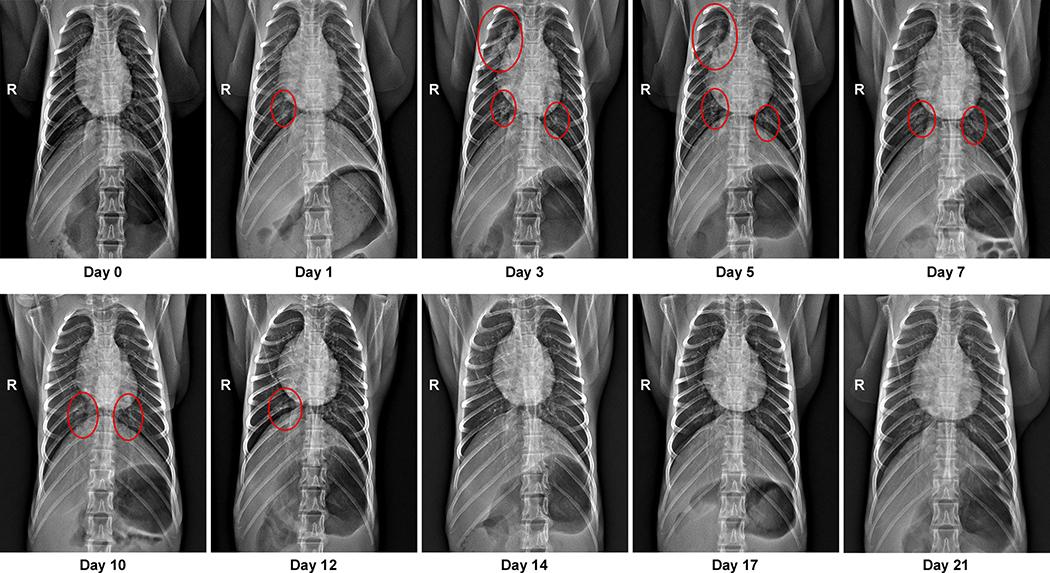

An outbreak of coronavirus disease 2019 (COVID-19), which is caused by a novel coronavirus (named SARS-CoV-2) and has a case fatality rate of approximately 2%, started in Wuhan (China) in December 2019. Following an unprecedented global spread, the World Health Organization declared COVID-19 a pandemic on 11 March 2020. Although data on COVID-19 in humans are emerging at a steady pace, some aspects of the pathogenesis of SARS-CoV-2 can be studied in detail only in animal models, in which repeated sampling and tissue collection is possible. Here we show that SARS-CoV-2 causes a respiratory disease in rhesus macaques that lasts between 8 and 16 days. Pulmonary infiltrates, which are a hallmark of COVID-19 in humans, were visible in lung radiographs. We detected high viral loads in swabs from the nose and throat of all of the macaques, as well as in bronchoalveolar lavages; in one macaque, we observed prolonged rectal shedding. Together, the rhesus macaque recapitulates the moderate disease that has been observed in the majority of human cases of COVID-19. The establishment of the rhesus macaque as a model of COVID-19 will increase our understanding of the pathogenesis of this disease, and aid in the development and testing of medical countermeasures.

2019 年冠状病毒病(COVID-19)疫情由新型冠状病毒(命名为 SARS-CoV-2)引起,病死率约为 2%,于 2019 年 12 月在中国武汉爆发。疫情在全球范围内迅速蔓延,世界卫生组织于 2020 年 3 月 11 日宣布 COVID-19 为大流行疾病。虽然人类 COVID-19 数据不断涌现,但 SARS-CoV-2 的发病机制有些方面只能在动物模型中进行详细研究,因为只有动物模型才能重复取样和组织采集。本研究显示,SARS-CoV-2 可引起猕猴发生持续 8-16 天的呼吸道疾病。肺部影像学显示肺部浸润,这是人类 COVID-19 的一个标志。我们在所有猕猴的鼻拭子和咽拭子以及支气管肺泡灌洗液中均检测到高滴度病毒载量;在一只猕猴中,我们观察到直肠排毒时间延长。总的来说,恒河猴复制了在大多数 COVID-19 人类病例中观察到的中度疾病。恒河猴作为 COVID-19 模型的建立将增进我们对该疾病发病机制的理解,并有助于开发和测试医疗对策。